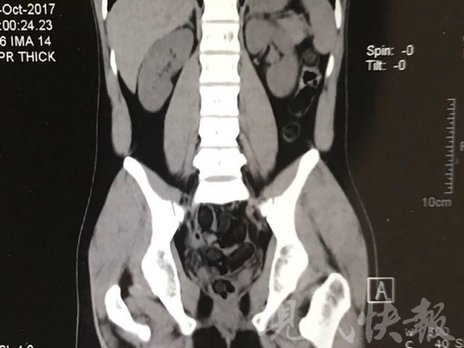

運毒小伙:希望被判處死刑

由于毒品在體內一旦泄露有可能致命,警方第一時間將阿永帶到醫(yī)院進行檢查。CT 掃描的結果顯示,阿永體內布滿了密密麻麻的白色圓柱狀固體,就像一粒粒的蠶蛹。在南京市公安局鼓樓分局二板橋派出所,阿永分四次排出了毒品,毛重369.99克。經(jīng)訊問,阿永交代了自己全部的犯罪事實。目前,阿永已被刑事拘留。